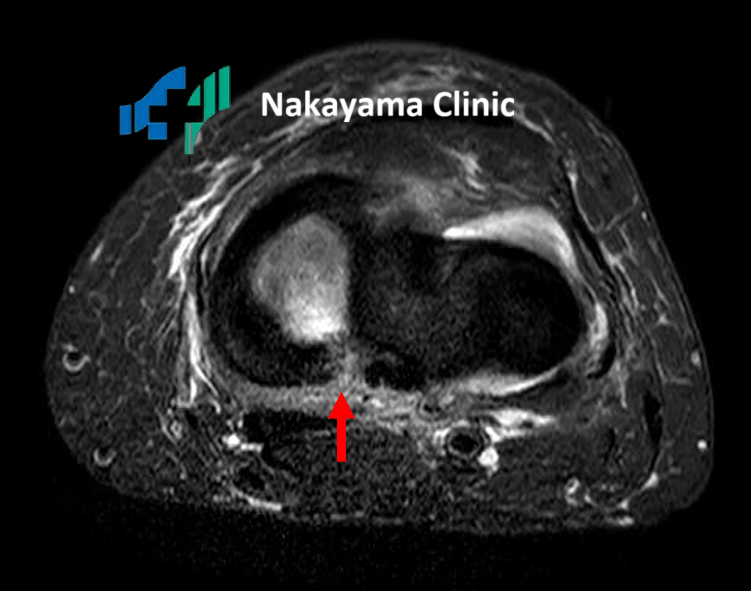

膝内側の骨髄浮腫 |

内側半月板後根損傷 |

膝の安定性を保つために重要な役割を果たしているのが、C型をした軟骨組織「半月板」と、骨と骨をつなぐ強靭な「靭帯」です。

スポーツや転倒などで膝をひねると、これらの組織が損傷し、「膝の裏が痛い」と感じることがあります。

特に、半月板の後ろ側(後根)が断裂すると、「ブチッ」という音とともに激痛が走り、急激に膝の状態が悪化することがあります。

これを見逃すと、骨が壊死(えし)してしまい、歩行が困難になるほどの痛みに発展する可能性も。

とても怖い損傷です。

膝内側の骨髄浮腫

内側半月板後根損傷